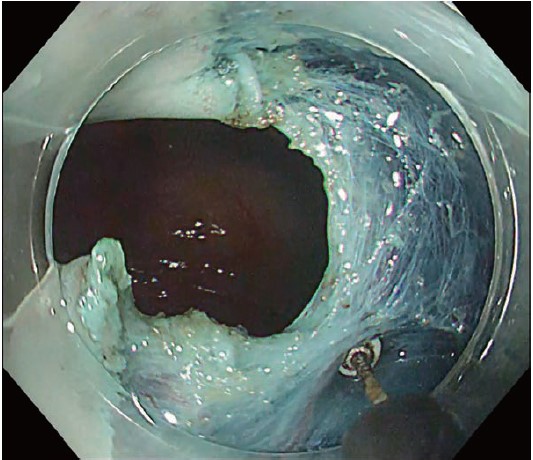

This case involved a 0-IIc lesion on the posterior wall of the mid thoracic esophagus, adjacent to a post ESD scar. Submucosal lifting was insufficient despite hyaluronic-acid injection (Figs. 9 & 10). Using an ultra-sharp DualKnife in this situation carries a measurable perforation risk and increases operator anxiety. Instead, a “push-through mucosal incision” with the small insulated tip of ITknife nano was chosen (Movie 2).

After lifting on the oral side of the scar, the tip was advanced and a blunt, controlled mucosal cut was made (Figs. 11 & 12). Once a full circumferential incision was complete, the remainder of the dissection was finished quickly and safely with the ITknife nano blade, achieving en-bloc resection in a short time.